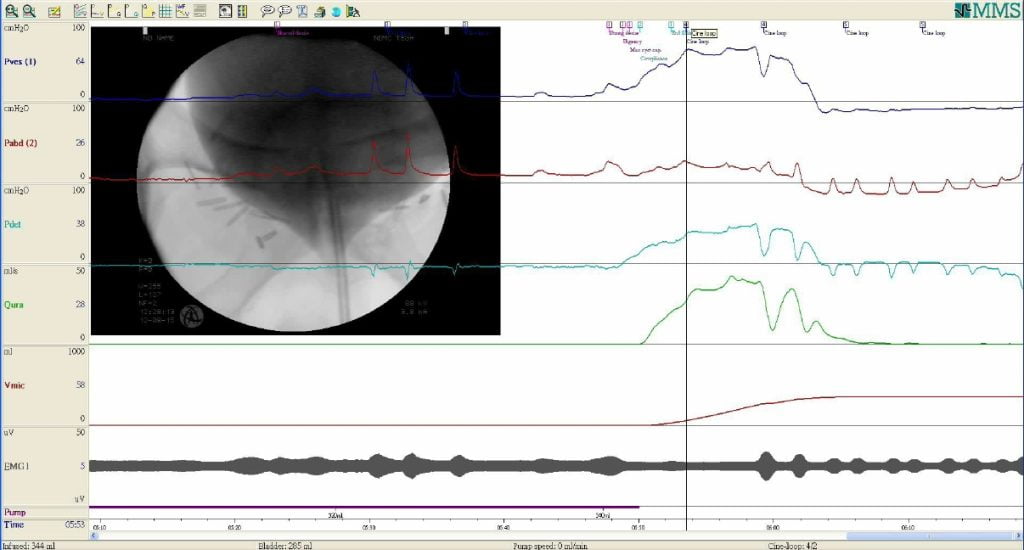

Urodinâmica é o estudo dos aspectos fisiológicos e patológicos envolvidos no armazenamento, transporte e esvaziamento da urina.

O estudo urodinâmico trata-se hoje de um poderoso método de investigação das disfunções miccionais. Sua finalidade é detectar as possíveis alterações funcionais que possam estar gerando os sintomas urinários ou a incontinência.

Convém lembrar que a urodinâmica, a despeito de ser um método cada vez mais empregado na investigação das incontinências, é um exame complementar, cujo resultado deve ser analisado e valorizado no conjunto de vários outros dados clínicos e/ou laboratoriais para se ter o diagnóstico final e escolher o melhor tratamento.

Estuda a relação entre o volume e a pressão da bexiga, avaliando a fase de enchimento vesical.

Para sua realização são utilizadas duas sondas vesicais para infusão de soro e medida da pressão intravesical, e uma sonda com balão de látex na extremidade que é  introduzida no reto para medida da pressão intra-abdominal. As sondas utilizadas são de pequeno calibre e introduzidas com gel anestésico tornando portanto, o preparo para o exame indolor. A sonda retal e uma das vesicais são conectadas a transdutores que transmitirão as pressões para o computador. Durante o enchimento vesical (da bexiga) são observados e anotados diversos parâmetros que serão registrados e analisados posteriormente.

Estudo miccional ou relação fluxo/pressão

Completado o enchimento vesical, a paciente volta à cadeira de fluxometria para novamente, esvaziar a bexiga. Esta etapa avalia o fluxo urinário em conjunto com as pressões vesical e abdominal, e tem por finalidade estudar a fase de esvaziamento vesical e a atividade do músculo detrusor e o fluxo urinário.